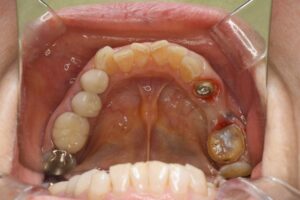

患者様は、奥歯4本の銀歯の色を変えたくて来院されました。虫歯の再発予防もしたいのでセラミックでの治療を希望されており、メリットデメリットと、起こりうるリスクについて説明の後、治療を開始しました。

ブリッジは欠損部分の両隣の歯を支えにするため、土台の歯には常に大きな負担がかかります。銀歯の場合、経年劣化による変形やセメントの流出によって、土台との間に隙間が生じやすく、そこから二次虫歯が進行して土台ごと失うリスクがありました。対してセラミックは変質せず、歯と強固に接着するため、細菌の侵入を許さず土台の歯をしっかり守り抜きます。

| 銀歯を除去し、ジルコニアブリッジにて補綴処置を行なった。 |